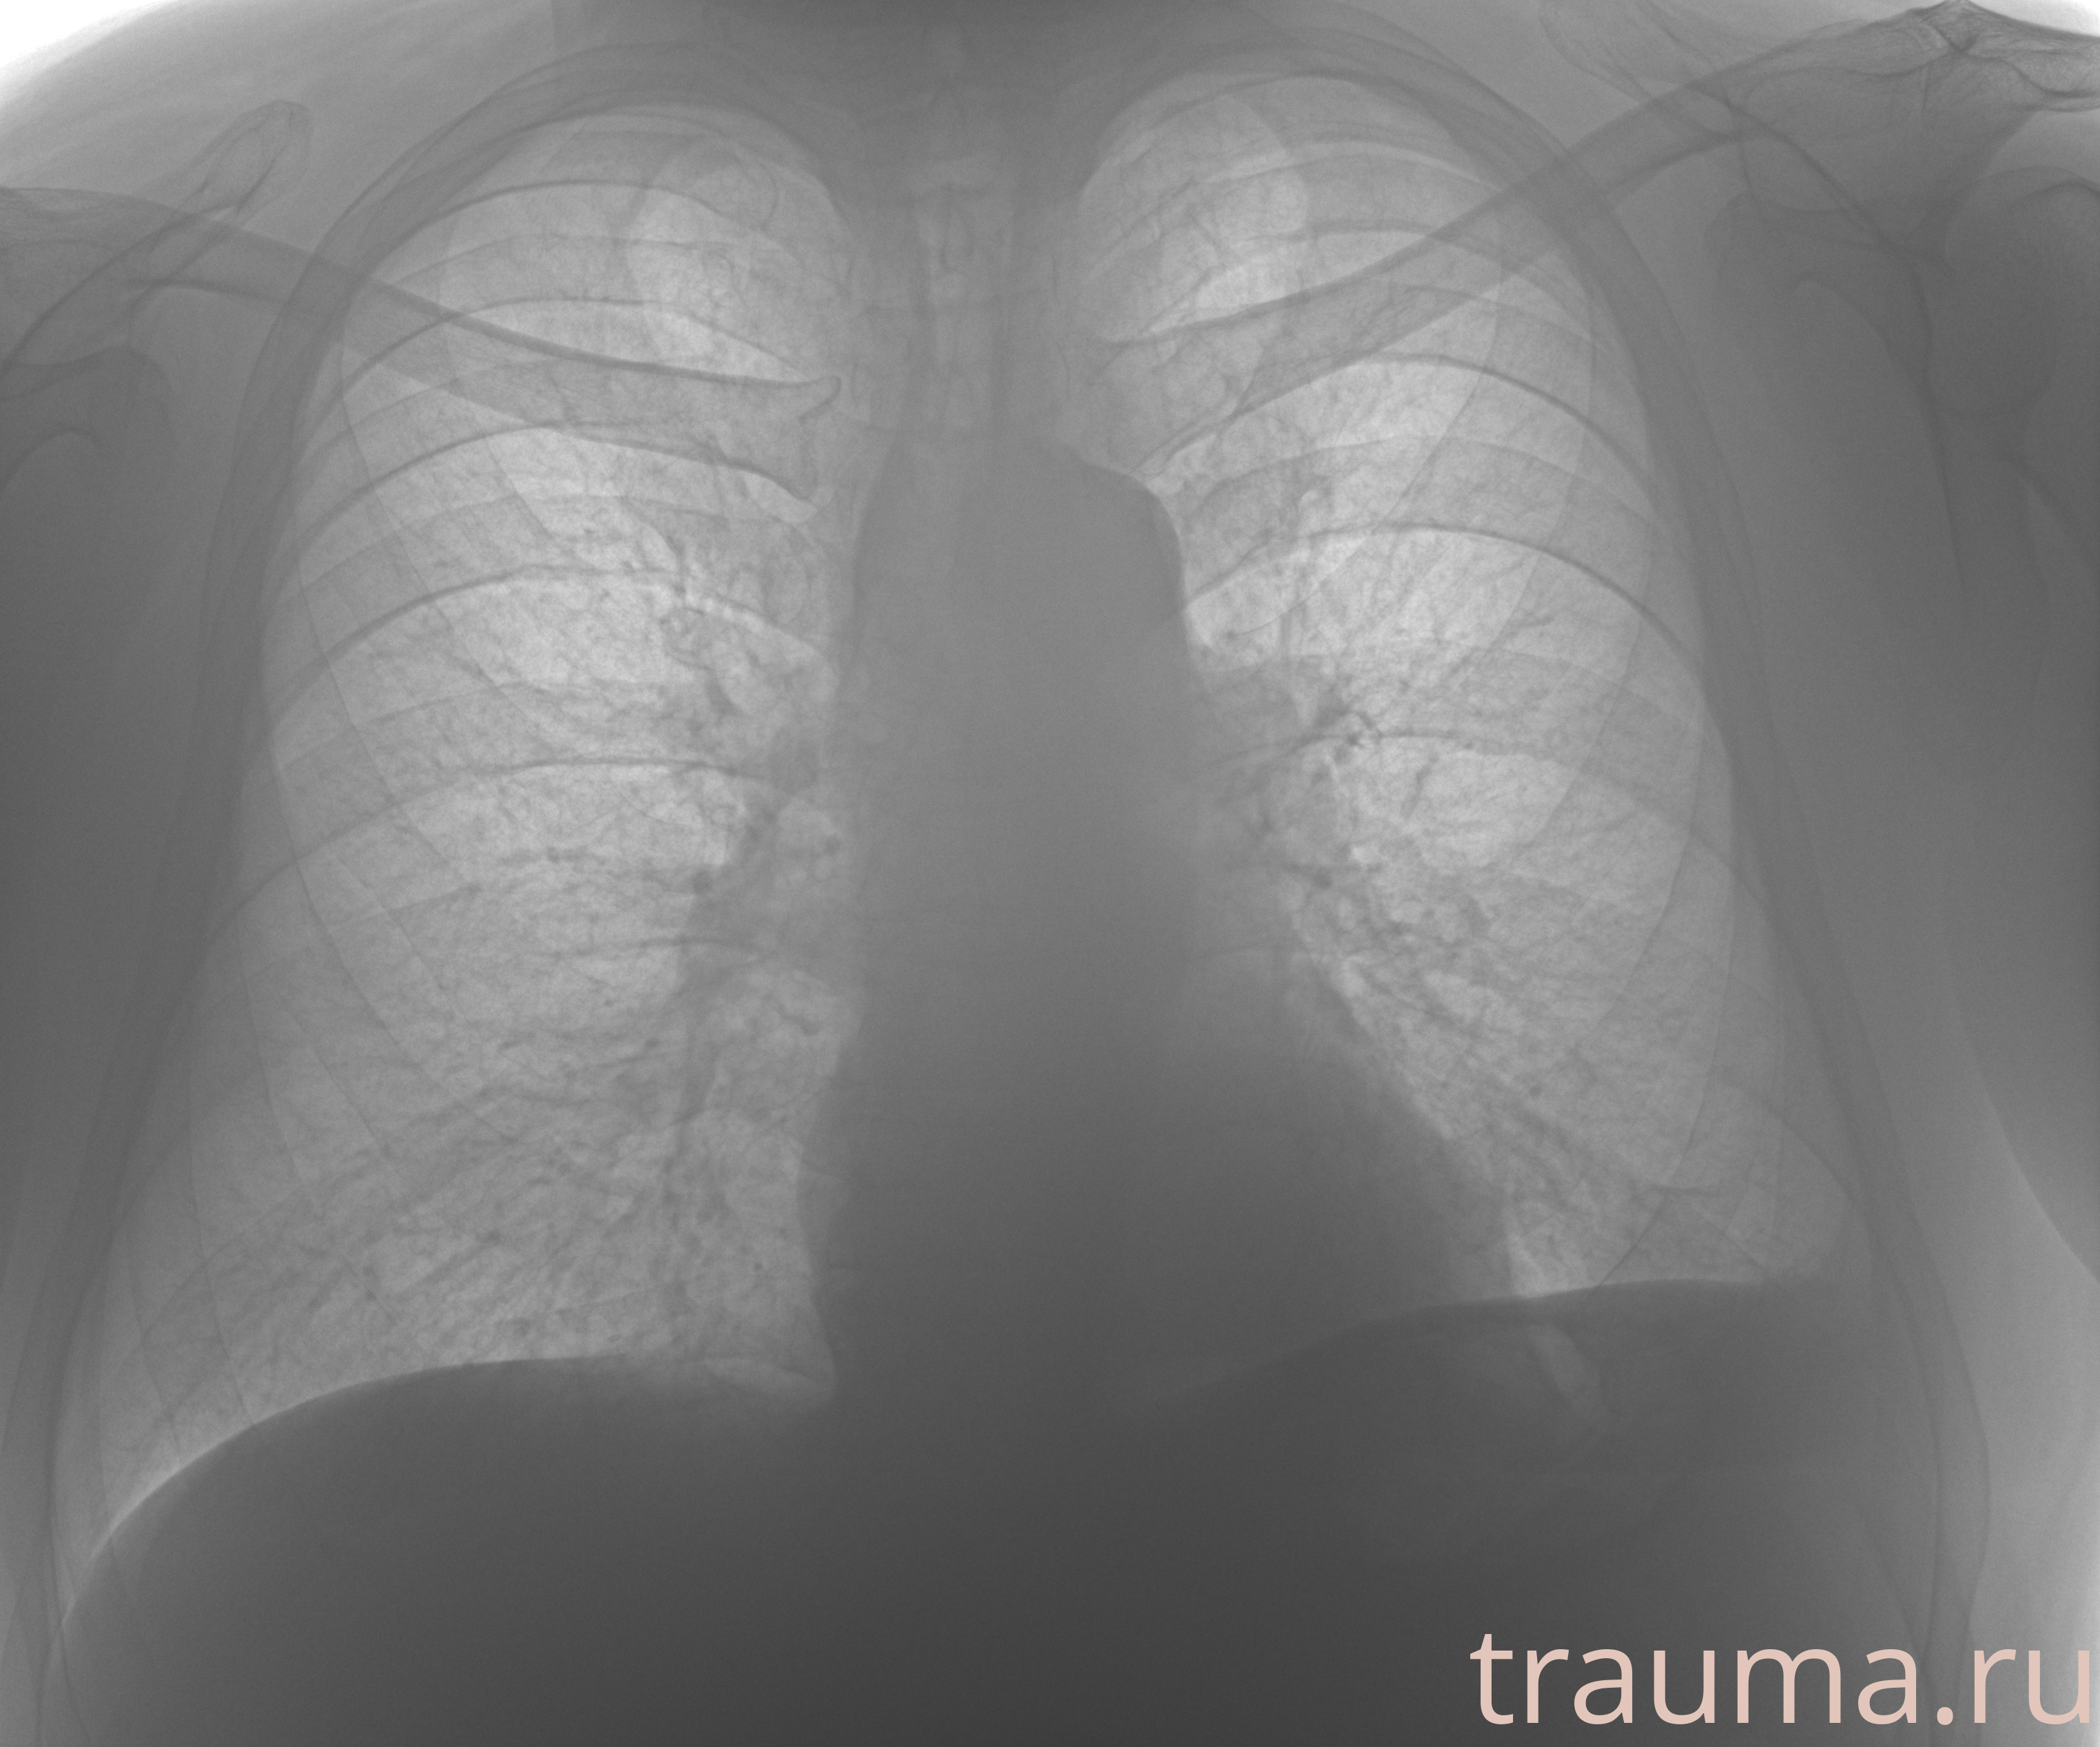

Рентгенограммы

Рентген на дому: по вашему адресу приезжает врач-рентгенолог, травматолог-ортопед с мобильным рентгеновским аппаратом, проводит диагностику травмы или заболевания, делает необходимые рентгенограммы, дает рекомендации по дальнейшему лечению. Получить качественные снимки в домашних условиях возможно благодаря уникальной методике, разработанной МосРентген Центром для института  Склифосовского

при переломе шейки бедра и пневмонии от компании МосРентген Центр - партнера Института имени Склифосовского